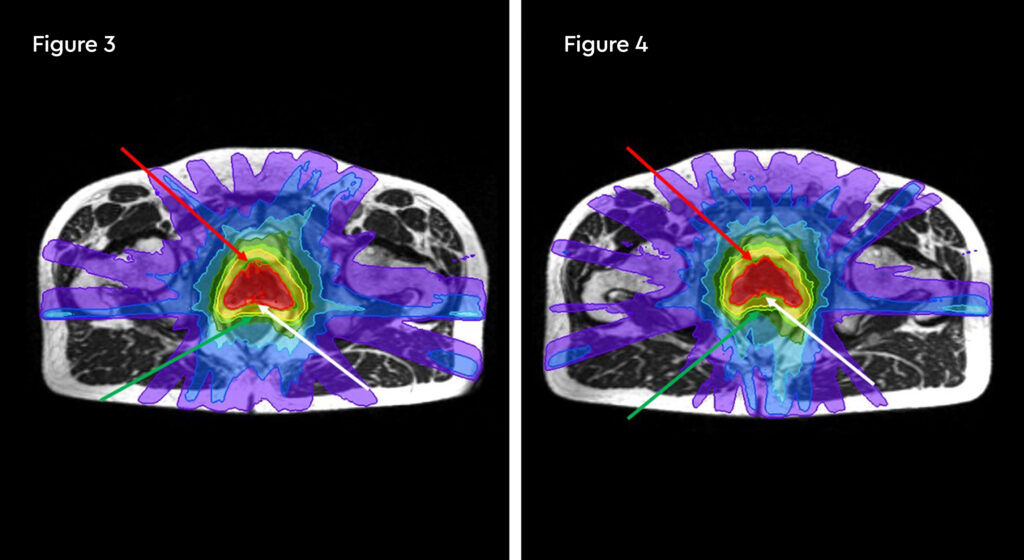

Figure 1: MR and PSMA PET fusion showing recurrence

Figure 2: Contouring target lesion

Figure 3: radiotherapy plan axial view

Figure 4: Radiotherapy plan 3D view